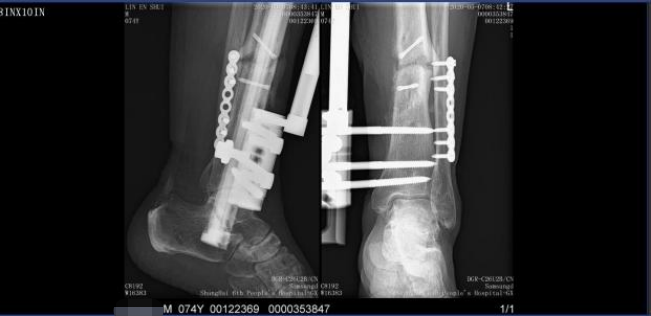

术前

术后

确定手术方案后,在与患者详细沟通及医护人员的精心准备下,医疗团队行左胫骨清创VSD+内固定去除术。术后5天创面炎症控制后,再行清创骨水泥填塞术。6周后,创面愈合,血常规、血沉、白介素等检查指标正常后行骨水泥去除+植骨+外支架固定术。术后骨折完全愈合。